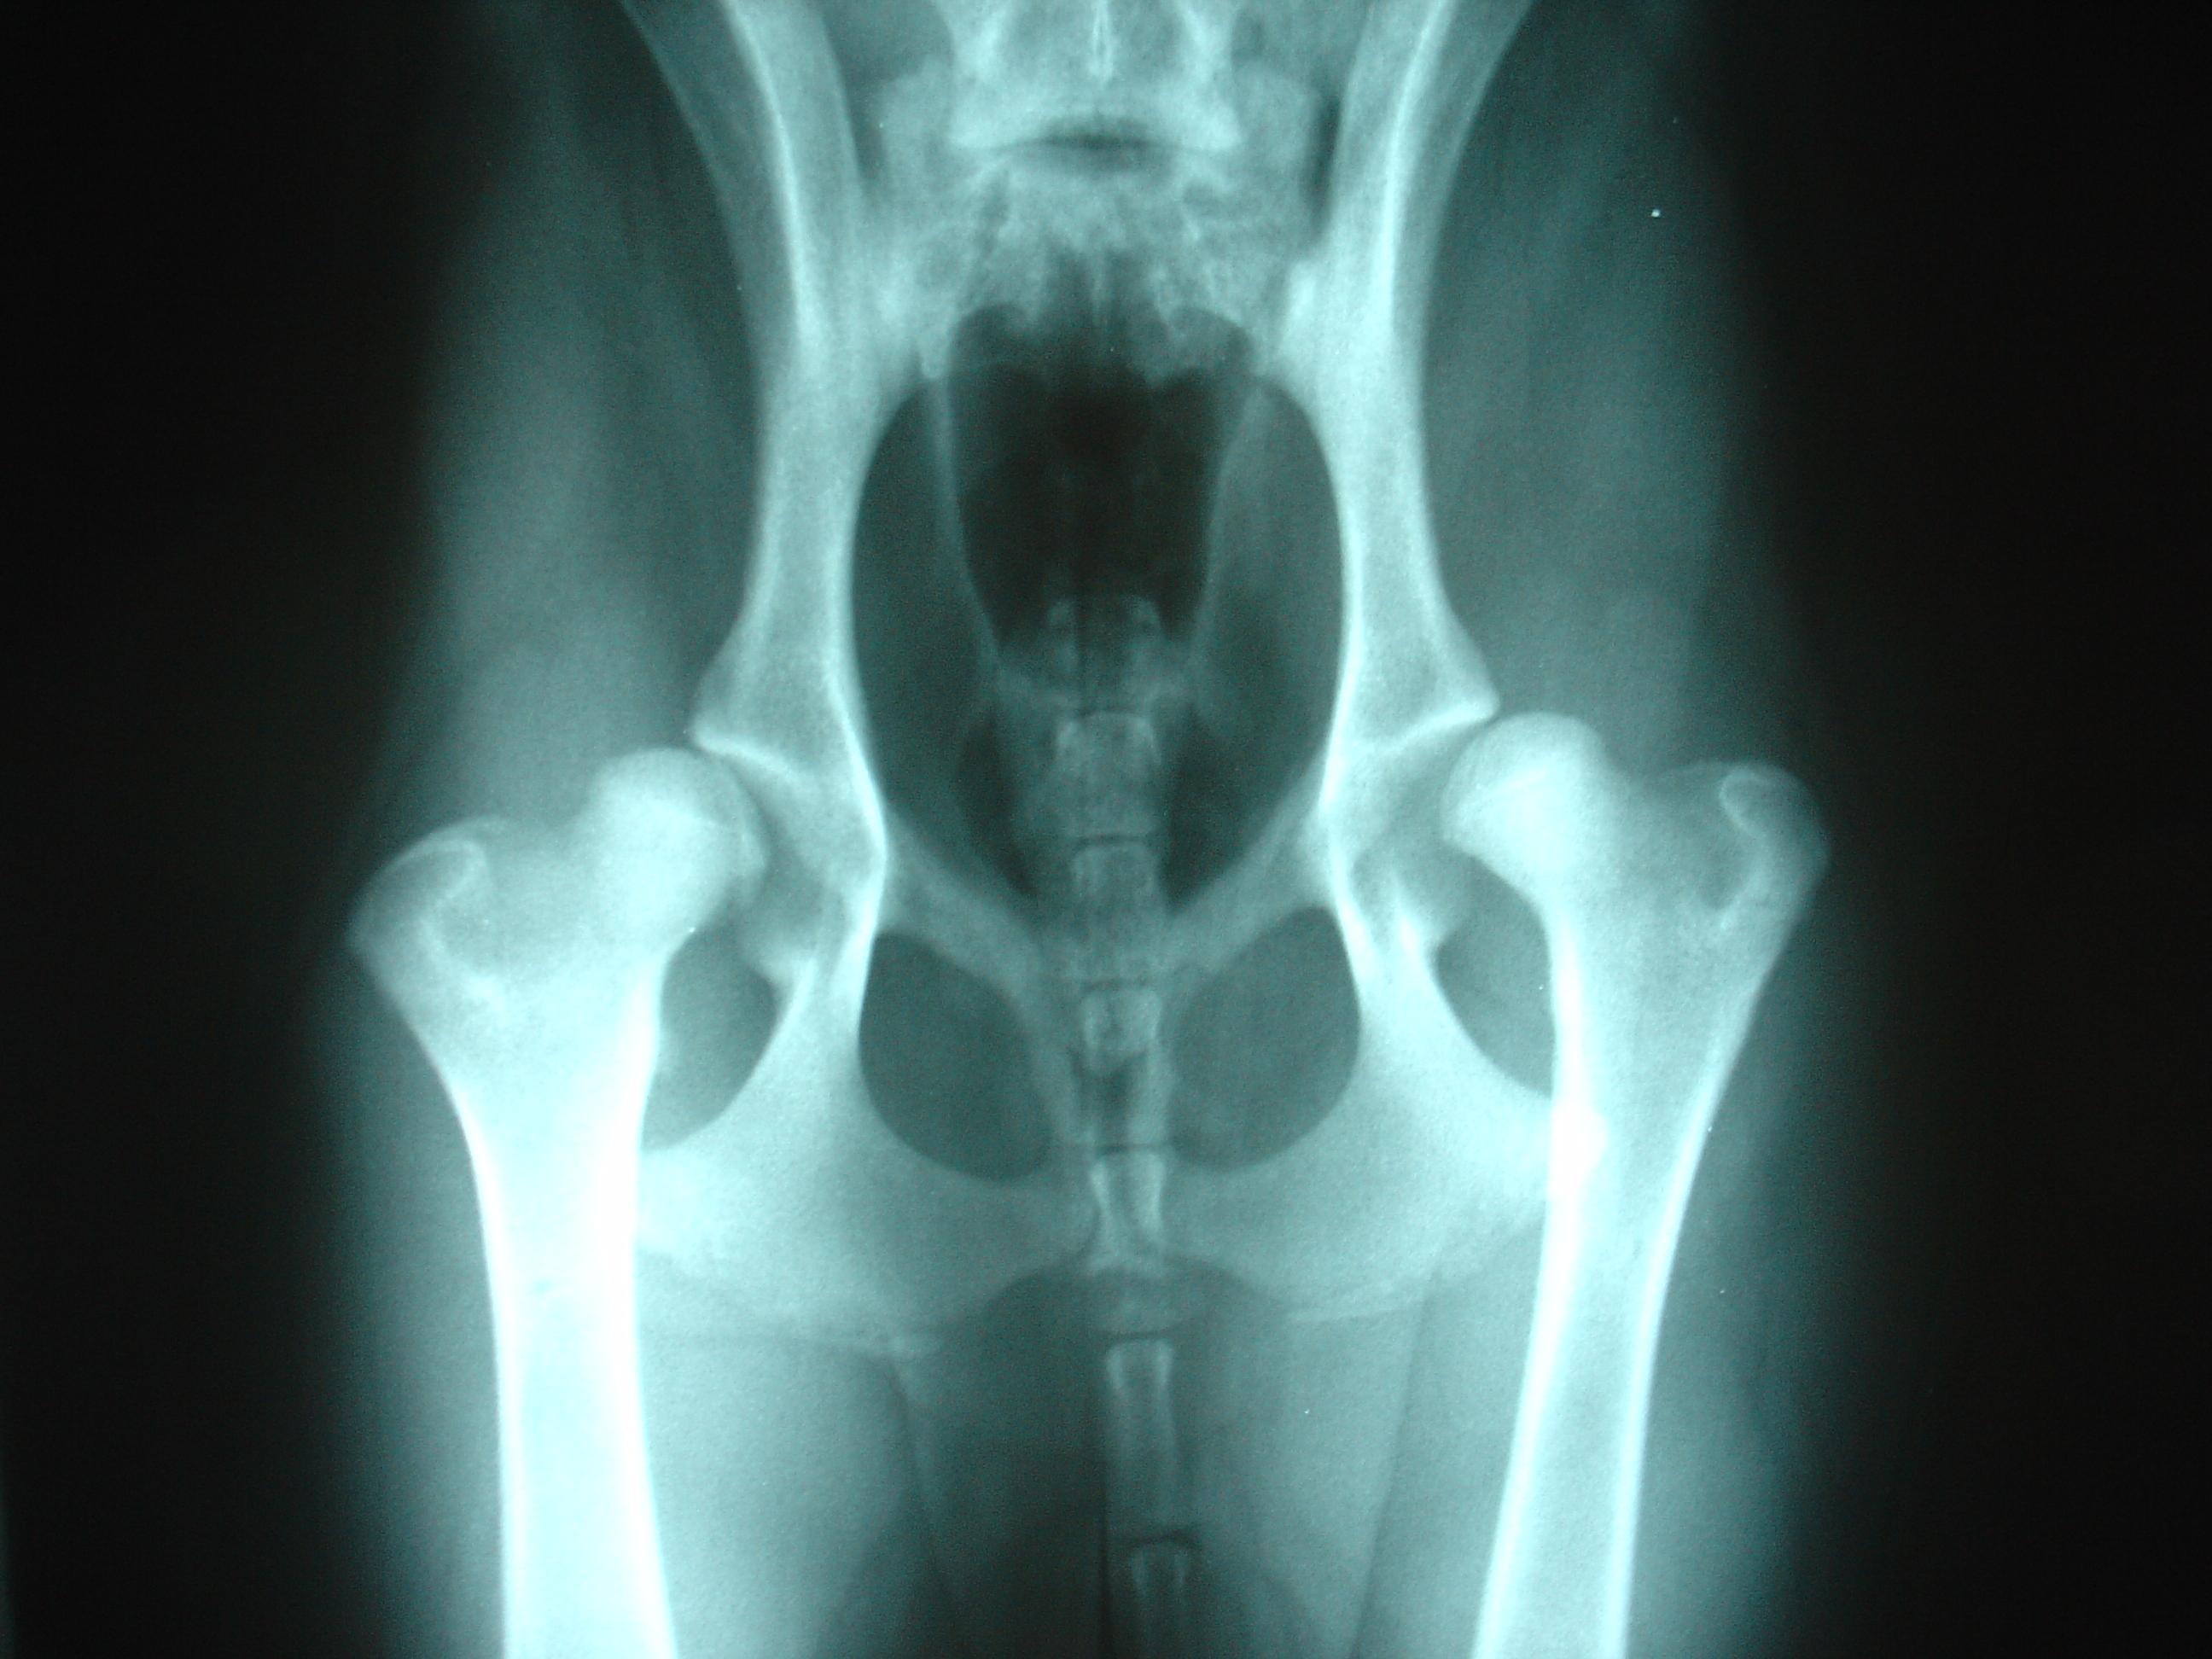

Actualmente, se distinguen cinco grados de displasia de cadera en perros, que clasifican la enfermedad en función de su gravedad, observables a través de una radiografía:

- Grado A: el perro tiene una cadera normal y, por tanto, no presenta signos de displasia.

- Grado B: existe una ligera sospecha de que el perro pueda padecer displasia.

- Grado C: la radiografía muestra signos leves de displasia.

- Grado D: existe una moderada displasia de cadera.

- Grado E: el perro sufre una displasia de cadera grave.

Si tu perro presenta algunos de los síntomas descritos anteriormente, podría tener displasia de cadera y debes llevarlo al veterinario para que haga el diagnóstico correspondiente. Durante el diagnóstico, el veterinario palpará y manipulará las caderas y la pelvis y solicitará una radiografía de esa zona. Para realizar la radiografía, es posible que sea necesario anestesiar al perro, ya que la misma debe hacerse con el animal tumbado boca arriba. Además, puede pedir análisis de sangre y de orina. El resultado de ese diagnóstico indicará si la afección es displasia de cadera u otra enfermedad.